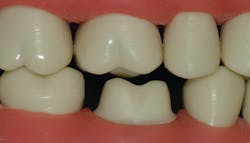

Most research information on crown preps states that an adequate tooth preparation has axial walls that extend 4 mm from the gingival margin to the occlusal table, and that the axial walls should be 20 degrees or less from the long axis of the tooth preparation. The depth of the marginal chamfer for a zirconia crown should be about 0.6 mm minimum for optimum strength. The occlusal reduction for a zirconia crown should be at least 1.5 mm or more to allow adequate strength of restorative material and optimum occlusal spacing of the crown occlusal contacts to produce a crown that is not too high when seated (figure 1).

Some labs are spacing the crown occlusal surfaces up to 500 microns (0.5 mm) out of contact to ensure you will not have to adjust the crown. This is far too much and places trauma on the adjacent tooth until the opposing and crowned teeth have extruded. Ideally, crowns should have perfect occlusion, but that is not likely. They should be spaced out of occlusion only a few microns to allow rapid tooth extrusion in a few days or a maximum of weeks. Seldom do you see these characteristics. Of course, sometimes tooth size and shape do not allow optimum preparations, but most of the time an optimum prep is possible.